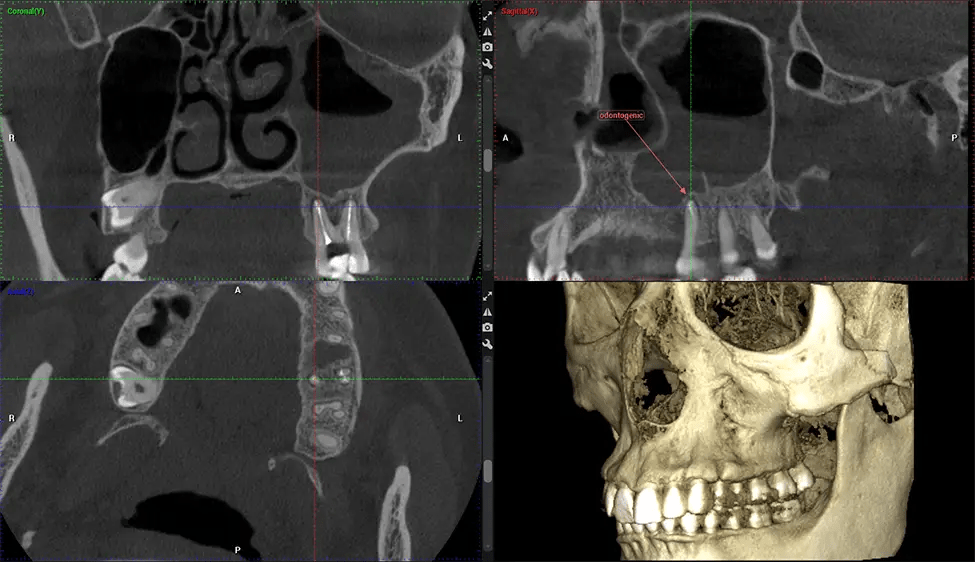

Cone Beam Computed Tomography (CBCT) is an advanced imaging technique used in dentistry and maxillofacial surgery to obtain detailed 3D images of the oral and maxillofacial structures. At Dr G Dental Studio, our CBCT scanners utilize a cone-shaped X-ray beam and a specialized detector to capture images from different angles. A computer then combines these images to create a 3D representation of the patient’s oral anatomy.

This 3D scan, called cone beam computed tomography, gives your dentist a more complete image of your oral anatomy and disease processes than a traditional X-ray. Unlike conventional X-rays, which capture a 2D image of your mouth from various angles, a 3D scan takes multiple digital X-rays for one image. It provides a complete view of your jaw, teeth, nerves, and soft tissues. This enhanced view allows dentists to detect minor issues not visible in traditional 2D scans, such as impacted wisdom teeth or bone fractures in the sinus cavity.

After the scanning process, the captured X-ray images are processed by the CBCT software, which applies algorithms to reconstruct a detailed 3D image of the scanned area. The software compiles these individual X-ray images and creates a digital 3D representation of the patient’s anatomy. The reconstructed 3D CBCT image can be viewed and analyzed by the dentist or radiologist. This image can be manipulated, rotated, and zoomed in or out to examine specific structures and evaluate the patient’s condition.